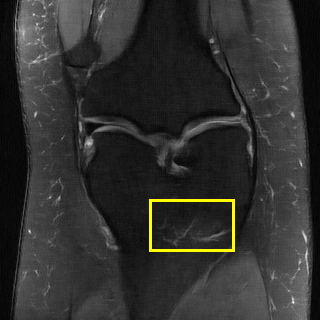

Edge preserving has always been a crucial concern in the design of reconstruction models. To improve the quality of reconstructed images and preserve image edges, some works suggested introducing edge priors in the original restoration problem to preserve image edges [4, 34]. However, they will suffer from complicated algorithm design and time-consuming training processes. Recently, some more efficient methods have been proposed to use edge maps as external guidance for image restoration. For example, Yang et al. [48] used off-the-shelf edge detectors to extract image edges from the degraded images. Fang et al. [12] predicted image edges by constructing an edge reconstruction network. Huang et al. [18] designed a novel dual discriminator GAN framework for solving fast multi-channel MRI, in which one GAN network is built for edge information enhancement. Inspired by these methods, we also consider introducing image edge prior as external guidance to MRI reconstruction since 1) image edges are prominent and distinguishable features in MRI (see Fig. 1), which can serve as a good guide to the model to recover high-frequency details; 2) the ground truth edges can be easily fetched via ordinary edge extraction operators, like Canny, Sobel, and Prewitt, which means that the edge maps can be learned in a data-driven manner. However, how to effectively utilize image edge priors to guide image reconstruction still remains a challenge. In some methods, edge information was simply concatenated with the input image and passed to the next stages. Though this is a simple way to utilize the edge priors, it may not give full play to the guiding role of the edge priors. Therefore, in this work, we want to explore a more efficient and effective mechanism to fully take advantage of image edge priors.

fastMRI is a large-scale MR dataset jointly established by Facebook AI Research and NYU Langone Health. It provides both knee and brain datasets for evaluation. In our work, we use the multi-coil knee dataset, which was acquired on three clinical 3T systems or one clinical 1.5T system using a 15-channel knee coil array. The dataset includes data from two pulse sequences, yielding coronal proton-density weighting with (PDFS) and without (PD) fat suppression. As is shown in Fig. 1, PD images usually contain more structural and prominent edge features than PDFS images, which suggests that it is more challenging to use edge guidance on PDFS datasets. Therefore, we explore the effectiveness of EAMRI on these two modalities. Following [13], for both PD and PDFS knee datasets, we separately filter out 227 volumes (8332 slices) for training and 24 volumes (1665 slices) for testing. The dataset is centrally cropped to .